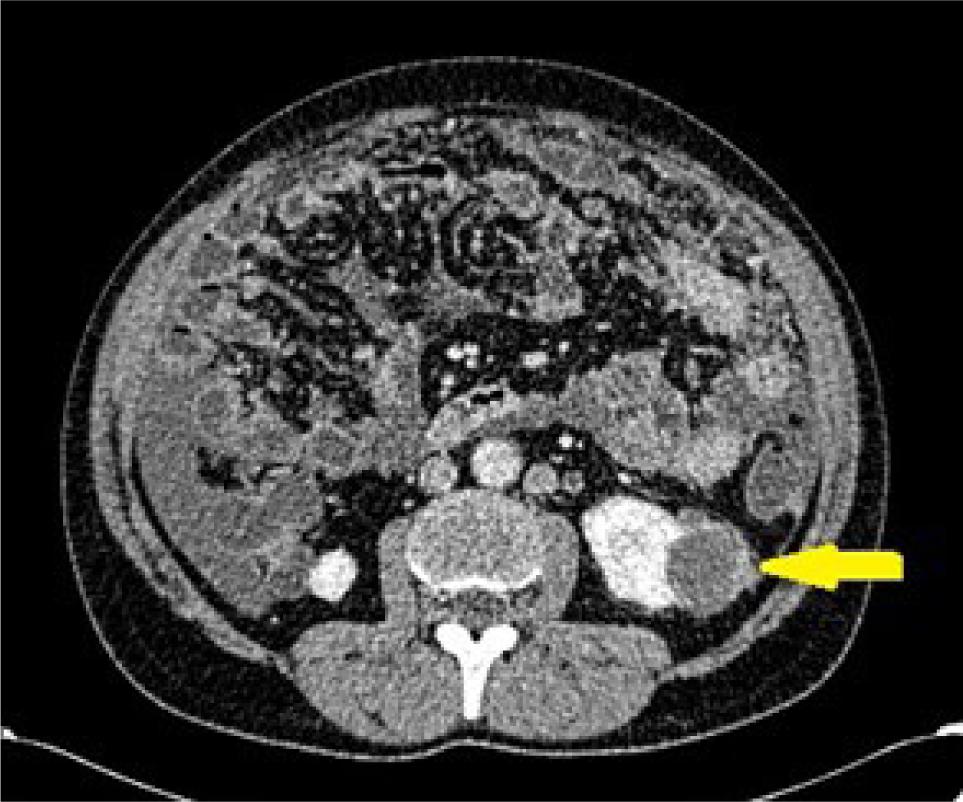

Figure 4: Axial CT at the level of renal hila in a 54-year-old female patient showing a partially solid mass lesion in the left kidney with enhancing small soft tissue component (arrow) and evident angular interface sign. The mass was resected and pathologically showed clear-cell renal cell carcinoma.